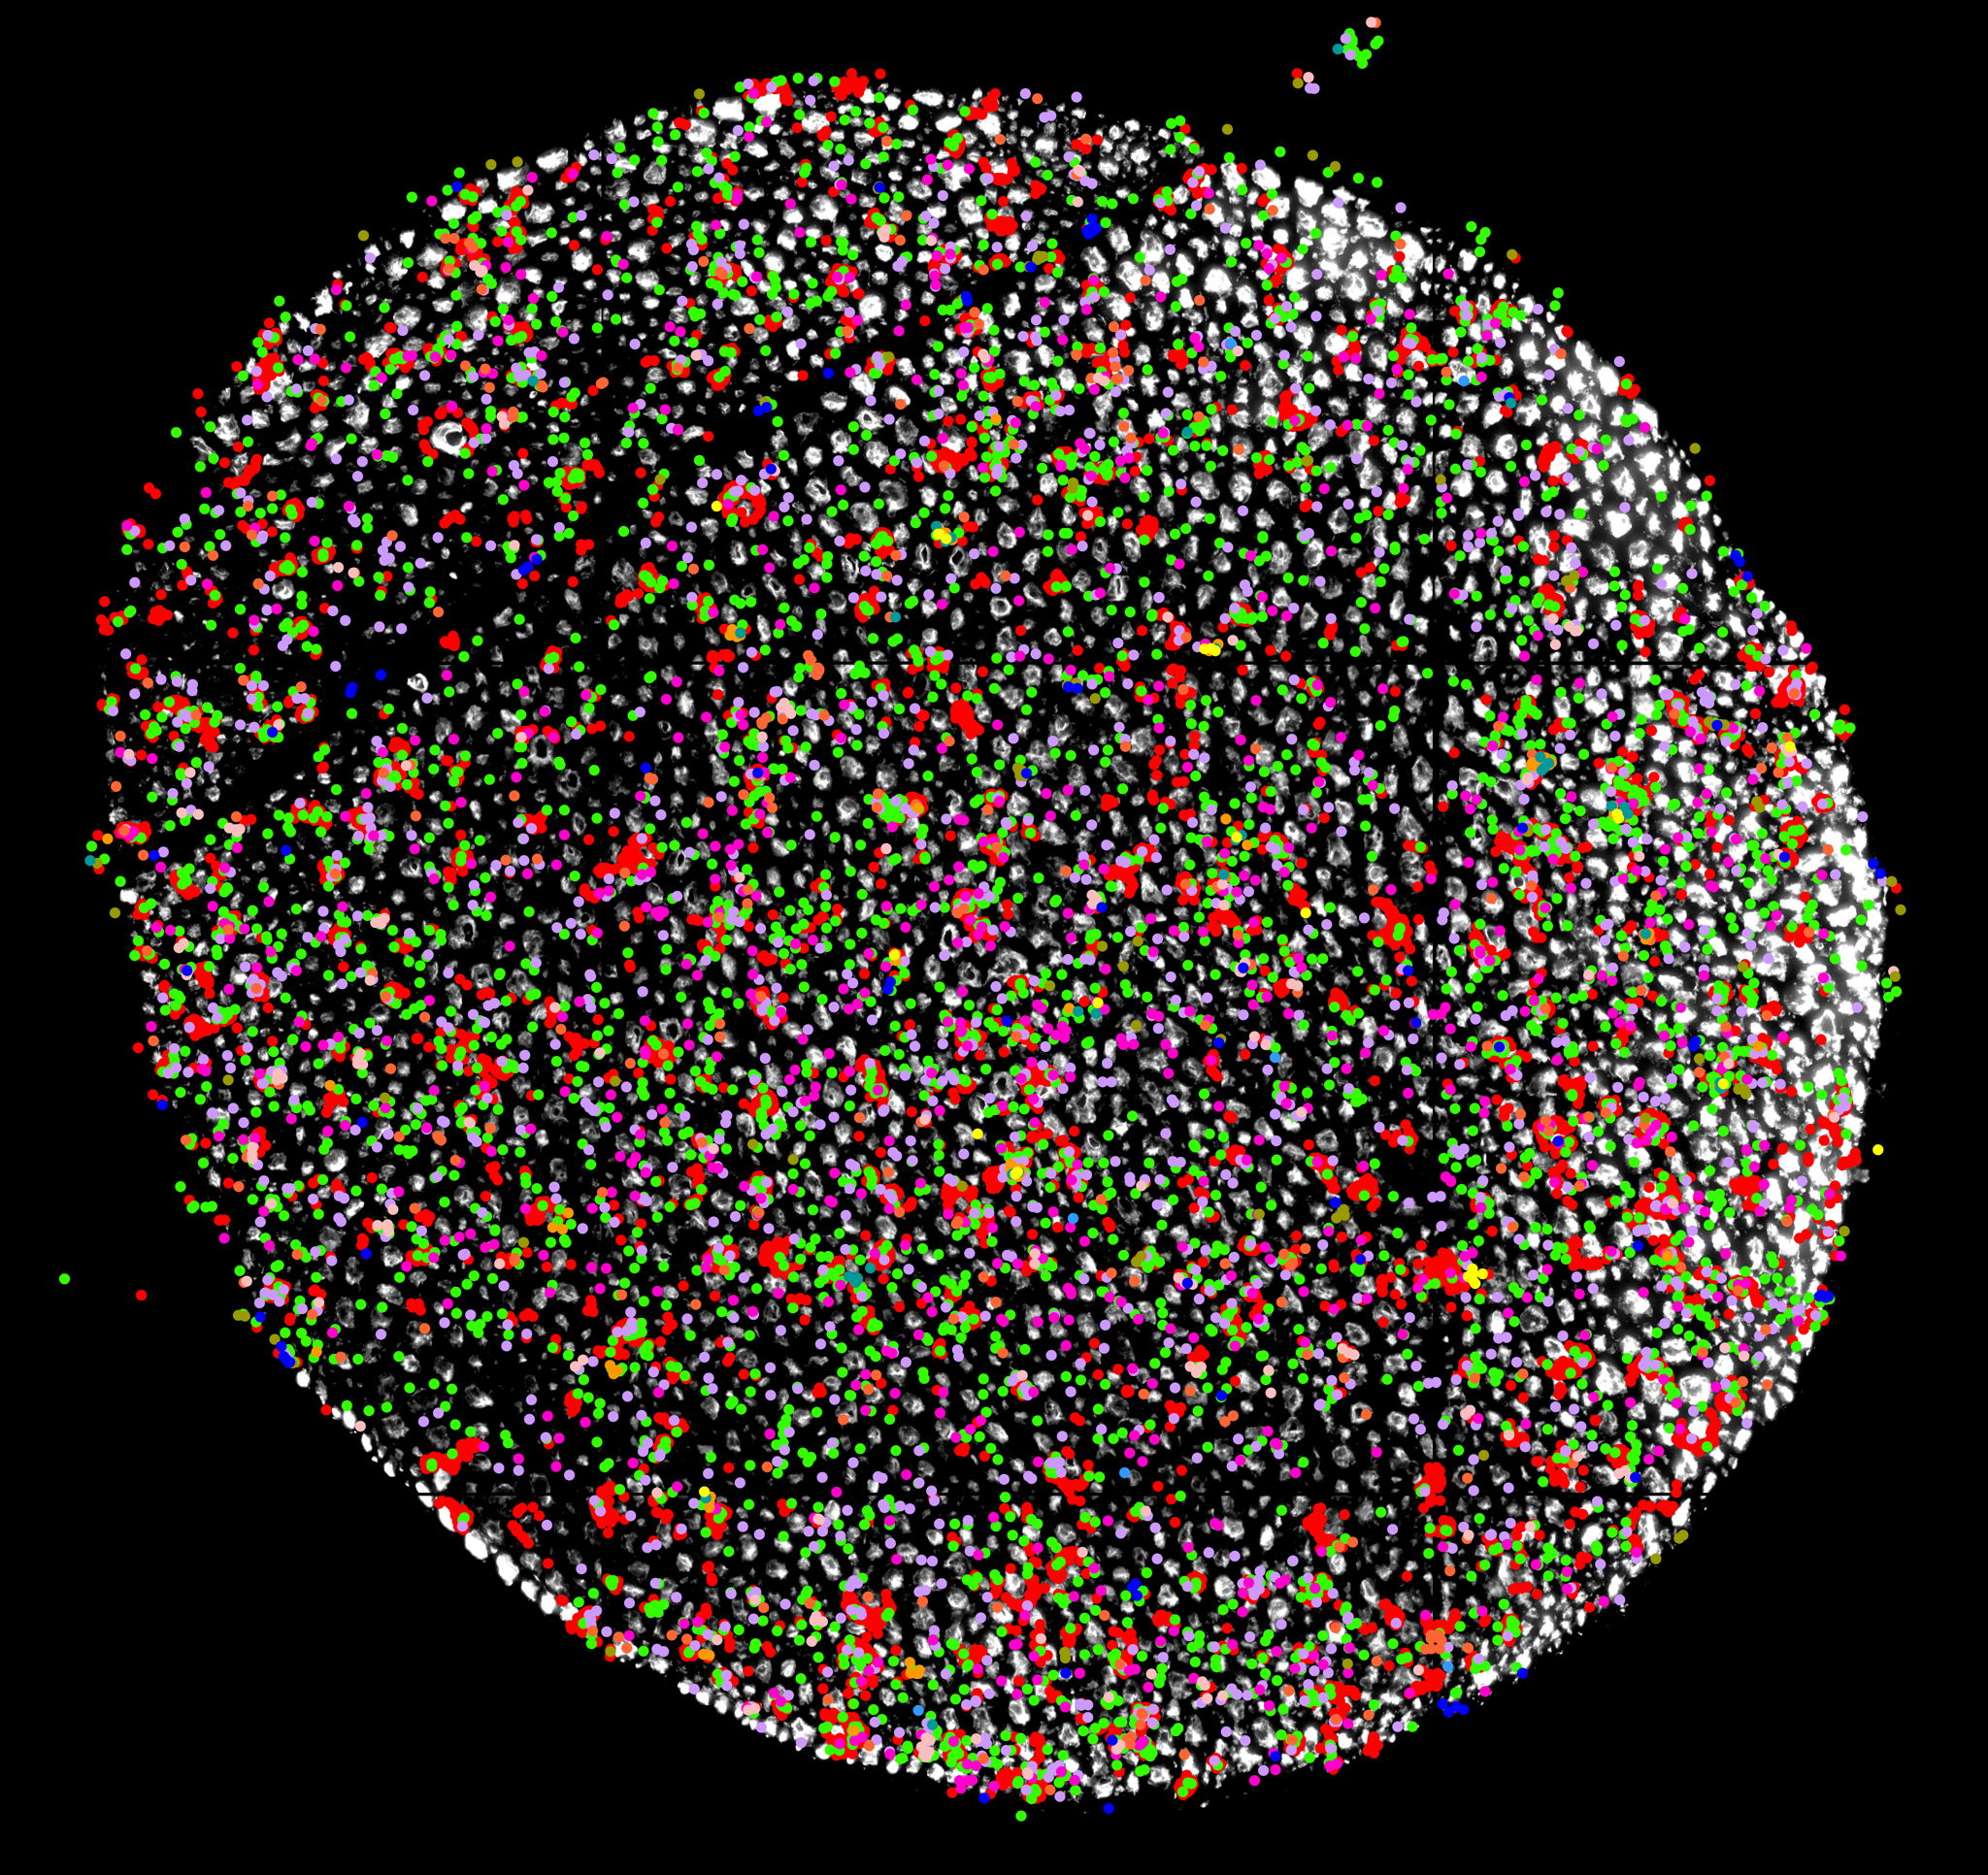

To address this, Dr. Baptiste Libé-Philippot, a Postdoctoral Fellow in the Vanderhaeghen lab, switched off SRGA2B and SRGAP2C in human neurons, transplanted them into mouse brains, and carefully monitored synapse development over an 18-month period.

“We discovered that when you turn off these genes in human neurons, synaptic development speeds up at remarkable levels," says Dr. Baptiste Libé-Philippot. "By 18 months, the synapses are comparable to what we would expect to see in children between five and ten years old! This mirrors the accelerated synapse development observed in certain forms of autism spectrum disorder.”